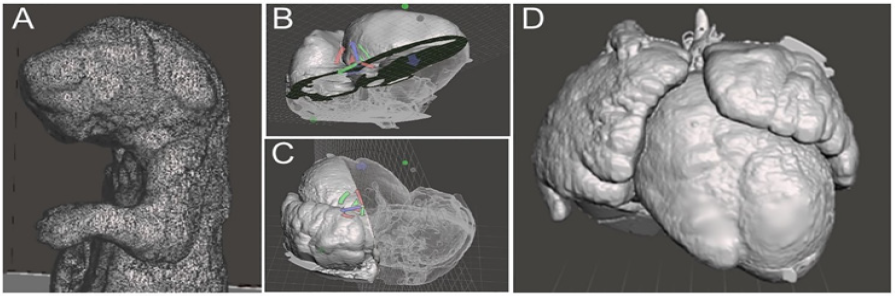

Figure 5: 3D surface rendering (A) 3D rendering of a mouse pup from micro-CT data with excessive mesh showing, highlighting the importance of optimization to reduce file weight (B, C) Examples of model slicing of a 3D rendering of a mouse heart from ECM source data file. (D) Exterior view of a 3D rendering of a mouse model heart with DORV.

There are countless other tools that can be used to edit the model if necessary, however these three are integral in optimizing the model. It was also observed that image stacks from ECM had dimensions on the scale of five to ten meters. This is an example of another incompatibility between preclinical imaging modalities and human modalities and can be fixed using the resize tool available in the Meshmixer software. It is a simple tool to manually resize the model by dragging the cursor. Ultimately, reducing the file size of the model gives it much more versatility, reducing time taken to view and edit the file, increasing compatibility with weaker computers, and increasing ease of file sharing with other computers. This final file can also be saved and used for digital phenotyping, as it is an accurate representation of the genetic model in 3D form. It can be sliced in any direction using the place cut tool to view internal cavities and deformities making it a very versatile model. In addition to printing physical models, the segmentation and rendering models can provide volumetric information. Figure 6 shows 3D rendering and segmentation outcomes from various mutant mouse brains from micro-MRI source data.

Two open source software programs were used to establish this pipeline and a workflow established. Horos 33, a 3D segmentation, visualization, and reconstruction software; and Meshmixer 34, a 3D model editing software, were used in this project develop the model. A method in Horos was developed to overcome the difference in textures between human and preclinical imaging modalities, ultimately resulting in a 3D surface rendering of genetic mouse model heart and brain defects. Meshmixer was then used to edit said models to correct file sizes and prepare models for 3D printing. Here we outline the work flow for 3D imaging processing of 3D modeling for micro-CT, micro-MRI, and ECM for 3D printing into three steps: (1) segmentation, (2) surface rendering, and (3) optimization (Figure 4). Each step is essential to creating a final product, being a 3D printed model that accurately displays the phenotype of a given genetic mouse model, that can then be used to gain a deeper understanding of defects present in genetic models.